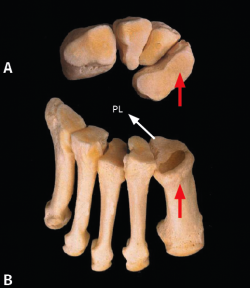

La carilla articular anterior del cuneiforme medial (C1) (Figura 1A) tiene una forma de croissant de concavidad externa con los extremos redondeados, siendo la parte superior más afilada y la inferior más ancha. Los extremos superior e inferior del croissant están ligeramente inclinados hacia delante, ejerciendo de topes óseos para frenar el movimiento de deslizamiento en sentido vertical. En el plano transversal, la superficie articular es convexa hacia delante.

Figura 1. A: carilla articular distal del primer cuneiforme; B: carilla articular proximal del primer metatarsiano. La flecha roja muestra fuerzas de compresión. La flecha blanca, fuerzas de tracción del peroneo largo (PL).

La superficie articular de la base del primer metatarsiano (M1) (Figura 1B) es congruente con C1. Tiene una forma triangular de vértice inferior: la parte superior, más ancha, es perpendicular al eje del primer metatarsiano y está preparada para soportar fuerzas de compresión. El vértice inferior, en forma de quilla, recibe la inserción del peroneo lateral largo y está preparado para soportar fuerzas de tracción(1).